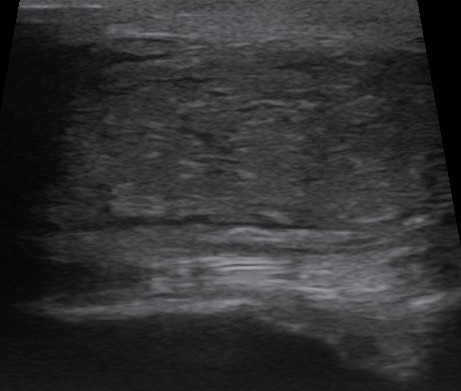

Det enda säkra sättet att ställa diagnosen är med gastroskopi – en kamera som förs in genom näsborren och ner till magsäcken. Eftersom magen måste vara tom fick Kakan svälta över natten och vara utan vatten de sista timmarna. Hon fick lugnande, och vi kunde försiktigt föra ner den tre meter långa slangen.

Hästens magsäck är liten och delad i två delar. Den övre delen har en kutan ”hudliknande” slemhinna utan skydd mot magsyran, medan den nedre körteldelen har celler som producerar slem. Hos Kakan hittade vi sår i båda delarna – hon diagnosticerades med EGUS – Equine Gastric Ulcerative Syndrome, samlingsnamnet för magsår.